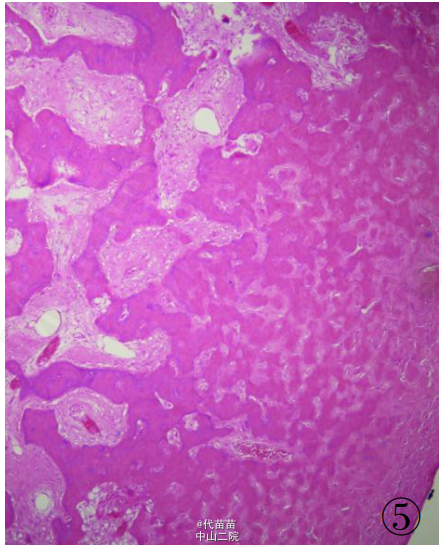

患者男性,40 岁。因体检发现肋骨肿块入院。患者无其它特殊症状,血生化检查基本正常,无放、 化疗史及Paget病史。CT检查示右侧第九后肋骨旁一团块状混杂高密度影,肿块边界尚清,位于肋骨表面,非髓内生长,向胸腔隆起,位于壁层胸膜与肋骨之间,与骨皮质有蒂相连(图 1、2)。临床考虑良性病变骨软骨瘤可能,遂行手术切除一段肋骨及表面肿块,送病理检查。 病理检查:眼观:送检肋骨1段,长9cm,宽2cm,骨表面隆起卵圆形肿块,4 cmX2 cmX2 cm 大小,质硬,切面灰白色,实性,与骨皮质有蒂相连,蒂部骨皮质浸润(图 3)。镜检:肿瘤由大量狭长且具平行排列倾向的高分化骨小梁构成,以编织骨为主,部分骨小梁已成熟为板层骨,大部分骨小梁周围缺乏成骨细胞被覆,部分区域已逐渐移行为有成骨细胞被覆的板层骨,瘤骨内可见骨重建过程中形成的粘合线,即所谓“Paget” 现象(图 4)。骨小梁间充满低细胞性纤维组织间质,梭形成纤维细胞形态温和,细胞核卵圆形,缺乏不典型性,部分肿瘤性骨小梁之间有脂肪髓形成,但无造血组织。肿瘤表面的骨样组织较幼稚,深部为相对成熟的粗大编织骨和板层骨(图 5),蒂部皮质和近皮质的髓腔内有局灶性肿瘤浸润(图 6)。肿瘤内含多灶性高分化软骨,软骨细胞排列紊 乱无极性,由于部分软骨位于肿瘤表面,故影像学和病理学类似骨软骨瘤改变。病理诊断:右侧第九后肋骨旁骨肉瘤。 骨旁骨肉瘤临床表现为骨表面缓慢生长的无痛性肿块,质硬,病程较长,可达数年。骨旁骨肉瘤预后较好,其5 年生存率达91% ,最佳治疗方案是大块肿瘤完整切除,切除范围应包括肿瘤周围的正常组织和软组织内的卫星病灶。若不完整切除则很容易复发。复发性肿瘤易发生去分化改变,称去分化骨旁骨肉瘤,其预后类普通型骨肉瘤,治疗原则和普通高级别骨肉瘤一致。 骨旁骨肉瘤可以说是骨肉瘤中的“异类” ,因为其不仅分化好,类似良性骨病,而且在骨表面生长,在病理诊断时须注意与以下三种良性骨病鉴别:(1)纤维结构不良。本例虽然部分肿瘤性编织骨呈不连续的字母状结构,在编织骨之间为高分化纤维,类似于纤维结构不良,但纤维结构不良是一 种纤维化生骨,伴有骨的成熟障碍,不会成熟为板层骨,也不会出现板层结构瘤骨在改建塑型过程中形成“Paget”现象。本例镜下见瘤骨比较成熟、 粗大,大部分相互连接成网,并有平行排列倾向,肿瘤表面骨样组织幼稚,深部较为成熟,并形成板层骨,成熟瘤骨内能见到“ 孕葬早藻贼” 现象。此外纤维结构不良均在髓内生长,不会在骨表面外生性生长,故影像学改变即可排除纤维结构不良。(2)骨软骨瘤。本例肿瘤内含有少量高分化软骨组织,由于部分软骨位于肿瘤表面,需与骨软骨瘤鉴别。骨软骨瘤蒂部的骨皮质常有缺损,肿瘤内的松质骨与宿主骨的正常松质骨相连续,二者相互融合。而骨旁骨肉瘤常环绕宿主骨在骨膜外生长,与髓腔不相通,肿瘤与骨密质之间有狭长的透亮带,即残存的骨膜;骨软骨瘤软骨帽下是由软骨化骨形成的松质骨小梁,骨小梁间隙内充满正常的造血性红髓或脂肪性黄髓,而缺乏骨旁骨肉瘤的成纤维细胞成分。同时骨旁骨肉瘤内的软骨组织、 结构和分布随意紊乱,缺乏骨软骨瘤明显的分层结构。(3)骨旁骨瘤。大多位于颅骨表面或副鼻窦内,分化成熟的骨小梁之间为脂肪细胞和小血管,缺乏纤维母细胞性间质。